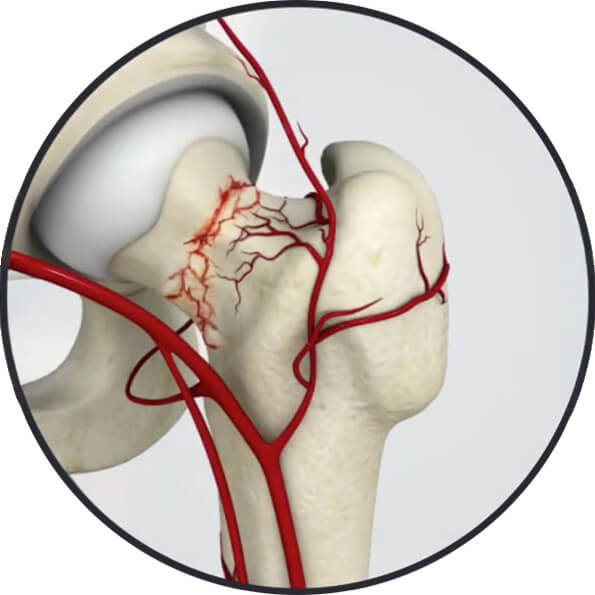

3 Fratura Descolada do Colo Femoral 4 Fratura do Colo Femoral / Vascularização

Fig. 3 - Fratura Descolada do Colo Femoral

Fig. 4 - Fratura do Colo Femoral / Vascularização